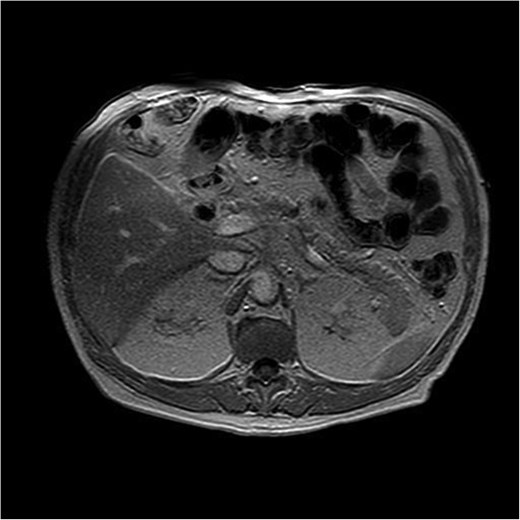

Magnetic resonance imaging revealed a hypointense lesion (2.6 × 1.7 cm) in the pancreatic body on T1-weighted sequences, with restricted diffusion and delayed contrast enhancement, findings suggestive of malignancy. Endoscopic ultrasound with fine-needle aspiration confirmed the diagnosis of acinar cell carcinoma. There was no evidence of vascular invasion, lymph node involvement, or metastases (Fig. 1).

T1-weighted MRI illustrating a hypointense nodular lesion in the pancreatic tail, measuring 24 × 20 mm. The lesion demonstrates restricted diffusion and delayed contrast enhancement, consistent with a neoplastic process suggestive of malignancy.